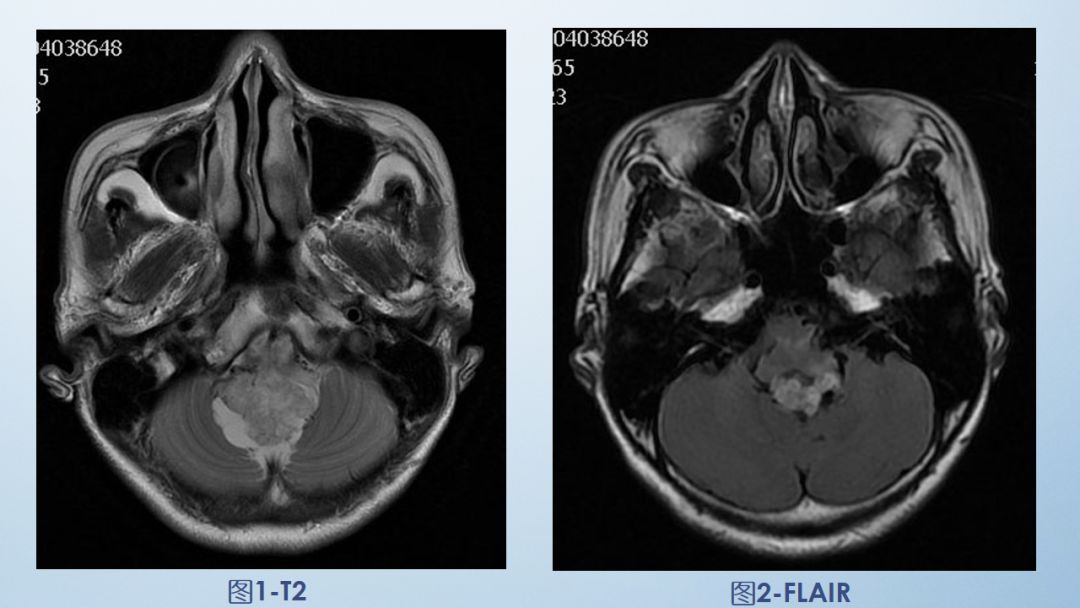

2-FLAIR

FLAIR图及T1矢状位增强:白色箭头所示小脑延髓池内可见实性占位病变,形态不规则,呈分叶状,病变边界清晰,边缘见血管流空信号影如蓝色箭头所示。

影像描述:小脑延髓池内见不规则异常信号影,呈等及稍长T1长T2信号,内部信号不均,边缘见稍粗大流空信号血管影,FLAIR病灶中心少许片状低信号,增强呈明显强化,DWI不均低信号,ADC不均高信号。小脑半球、延髓、第四脑室受压变形。临近延髓受压变窄,呈长T1长T2信号。

影像诊断:后颅窝实性占位病变,斟酌实性血管母细胞瘤。